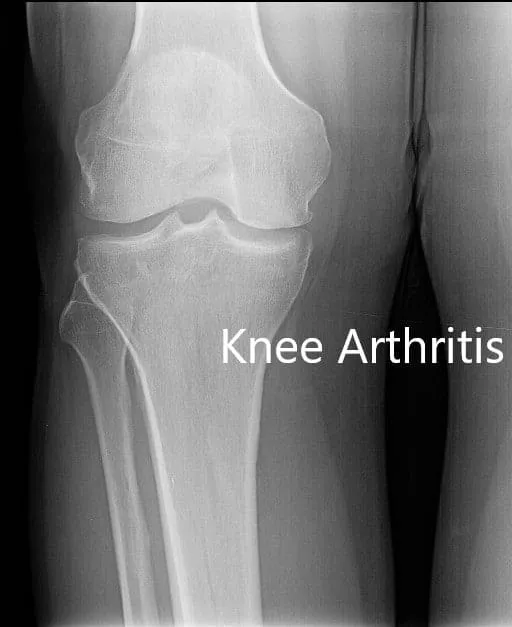

Los estudios de imagen revelaron osteoartritis tricompartmental con cambios degenerativos. Le recomendaron un reemplazo total de rodilla a medida en función de su examen y necesidades. Se debía realizar una tomografía computarizada preoperatoria unas semanas antes de la cirugía.

Radiografía preoperatoria que muestra la visión AP y lateral de la articulación de la rodilla derecha, y vista del horizonte de ambas articulaciones.